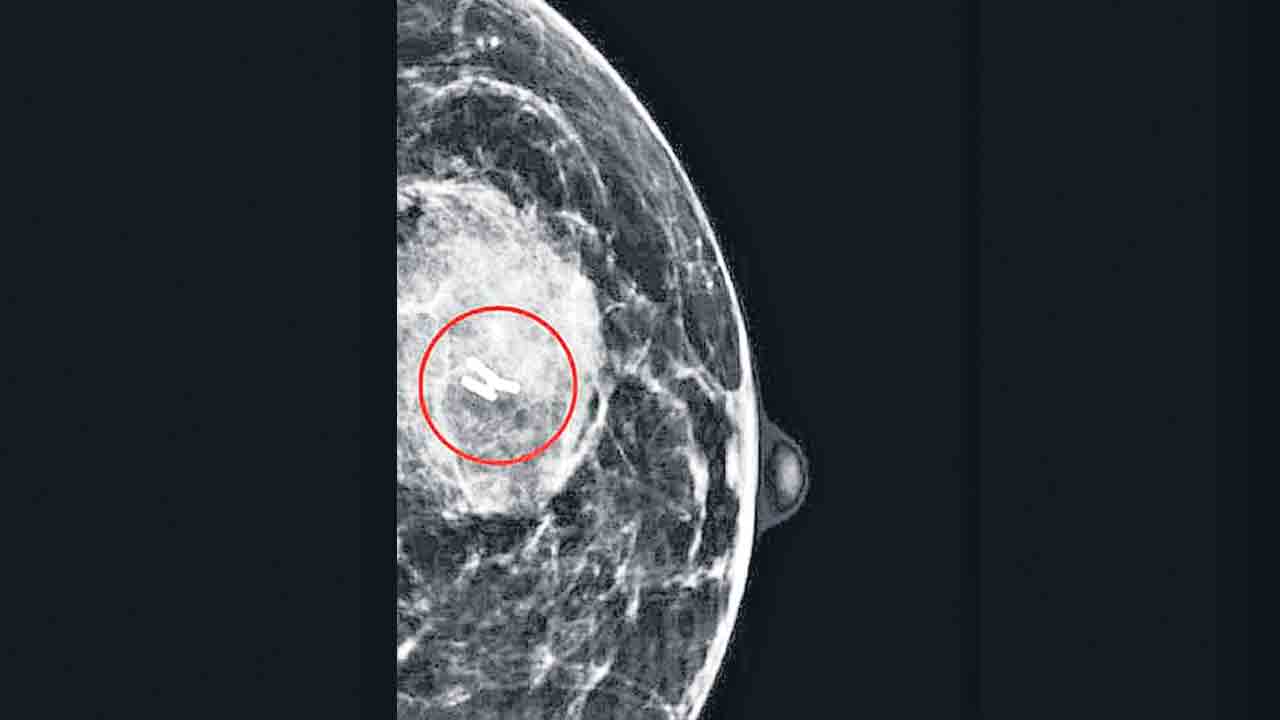

రొమ్ము క్యాన్సర్ బాధితుల్లో పూర్తి స్థాయిలో కణతులను తొలగించేందుకు కేరళకు చెందిన వైద్యులు సరికొత్త విధానాన్ని అభివృద్ధి చేశారు. క్యాన్సర్ బాధితుల్లో కీమోథెరపి చేసిన తర్వాత కొన్ని కణతులు మిగిలిపోతాయ